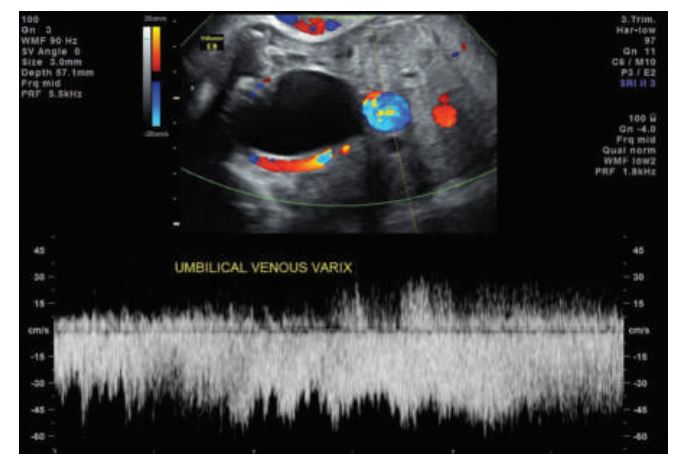

_________ the umbilical vessels affecting the umbilical artery and vein, respectively. Focal dilation of the umbilical vein is nearly always intraabdominal, but extrahepatic in location.

A varix appears on sonography as a dilated intraabdominal, extrahepatic portion of the umbilical vein. Color Doppler shows continuity with the umbilical vein.

Aneurysm and varix are focal dilations